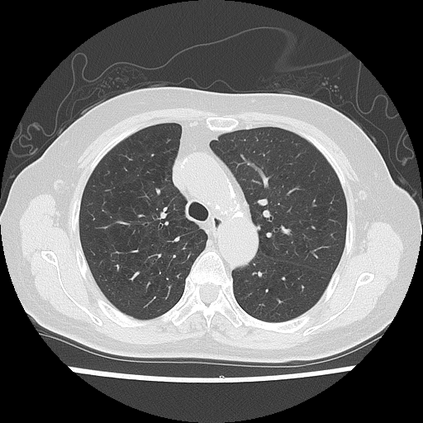

We propose a novel continual self-supervised learning (CSSL) framework for simultaneously learning diverse features from multi-window-obtained chest computed tomography (CT) images and ensuring data privacy. Achieving a robust and highly generalizable model in medical image diagnosis is challenging, mainly because of issues, such as the scarcity of large-scale, accurately annotated datasets and domain shifts inherent to dynamic healthcare environments. Specifically, in chest CT, these domain shifts often arise from differences in window settings, which are optimized for distinct clinical purposes. Previous CSSL frameworks often mitigated domain shift by reusing past data, a typically impractical approach owing to privacy constraints. Our approach addresses these challenges by effectively capturing the relationship between previously learned knowledge and new information across different training stages through continual pretraining on unlabeled images. Specifically, by incorporating a latent replay-based mechanism into CSSL, our method mitigates catastrophic forgetting due to domain shifts during continual pretraining while ensuring data privacy. Additionally, we introduce a feature distillation technique that integrates Wasserstein distance-based knowledge distillation (WKD) and batch-knowledge ensemble (BKE), enhancing the ability of the model to learn meaningful, domain-shift-robust representations. Finally, we validate our approach using chest CT images obtained across two different window settings, demonstrating superior performance compared with other approaches.